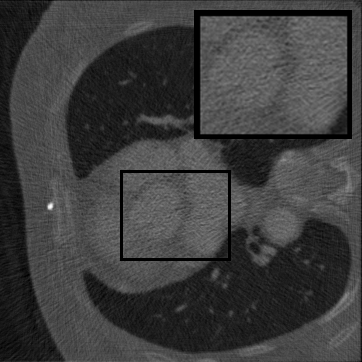

Figure 3: Visual comparison on TomoBank and LoDoPaB under random masking (ratio = 0.8). Rows 1 and 3 show the inpainted sinograms, while Rows 2 and 4 present the corresponding FBP [ramachandran1971three]-reconstructed images.

Table 1 summarizes the quantitative performance of FCDM and all baselines on the TomoBank and LoDoPaB datasets under both random and periodic masks. Figure 3 presents qualitative comparisons at a mask ratio of 0.8, showing both the inpainted sinograms and the reconstructed images obtained using FBP [ramachandran1971three]. Across all settings, FCDM consistently achieves the highest SSIM and PSNR values, demonstrating its strong capability in recovering structural details and suppressing noise-induced artifacts. Visual results in Figure 3 further confirm that FCDM produces smoother and more consistent sinograms, while other methods often exhibit angular streaking or local inconsistencies.